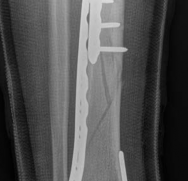

Complex Tibial Shaft Fracture: Plate Fixation for Plafond Extension

We review everything you need to understand about Complex Tibial Shaft Fracture: Plate Fixation for Plafond Extension. A **tibial shaft fracture** extending into the plafond is a complex injury characterized by a displaced, often multifragmentary break in the midshaft of the tibia that also involves the ankle joint's articular surface. These severe fractures commonly require immediate fasciotomy if compartment syndrome is present, followed by open reduction and internal fixation (ORIF) to restore anatomical alignment and joint function.

When a diaphyseal fracture propagates into the distal articular block, the injury transcends the typical treatment algorithms reserved for isolated tibial shaft fractures. Intramedullary nailing, the gold standard for diaphyseal fractures, becomes fraught with complications such as articular malreduction, propagation of intra-articular fracture lines, and inadequate distal fixation. Therefore, plate fixation—often utilizing minimally invasive percutaneous plate osteosynthesis (MIPPO) techniques—emerges as the primary definitive treatment modality. In the setting of an AO/OTA 43C3.3 fracture, where the articular surface is multifragmentary and completely dissociated from the diaphysis, the surgeon must meticulously reconstruct the joint surface before bridging the diaphyseal segment.